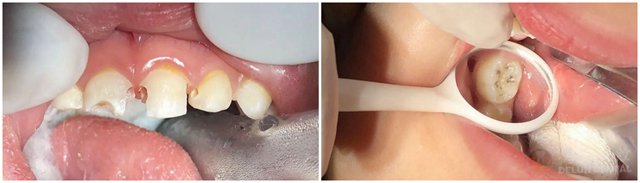

那么,哪些小朋友适合做儿童舒眠麻醉诊疗呢?张景棋医生介绍到,1. 极度恐惧儿童,患儿无法配合常规口腔治疗者;2. 患儿有多颗牙需要治疗,且无多次就诊条件(如外地,家离医院太远);3. 患儿有智力或全身疾病等方面的问题(比如自闭症、脑瘫,智力障碍等);4. 监护人担心捆绑束缚下牙齿治疗可能会对患儿心理造成伤害,使用全身麻醉可以保护其心理免受伤害并避免医疗危险。